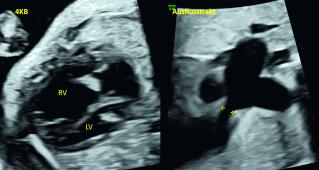

Bis dahin normaler Schwangerschaftsverlauf und keine anamnestischen Besonderheiten. Sowohl der 4-Kammerblick (4KB) als auch der Ausflusstrakt sind auffällig. Was vermuten Sie? Welche Herzseite ist betroffen?